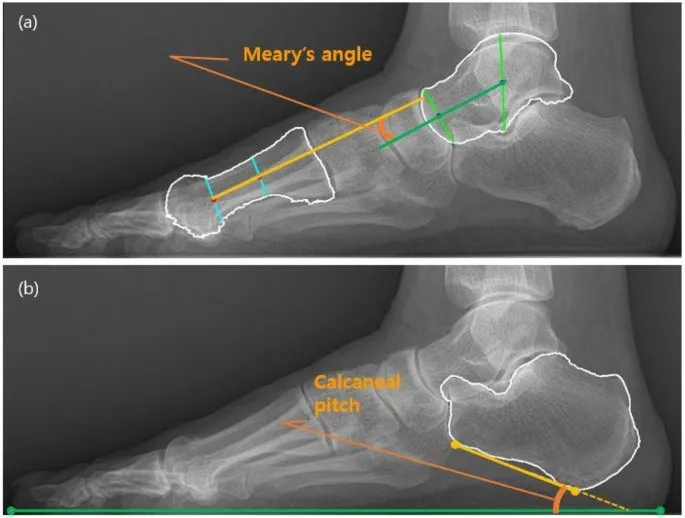

💡 Master This: The Meary's line (talar-first metatarsal angle) should measure 0-4° on lateral radiographs. Values >15° indicate significant flatfoot deformity requiring surgical correction. This single measurement predicts 90% of surgical outcomes in adult acquired flatfoot deformity.

📌 Remember: "ANGLES" for critical measurements - Anterior distal tibial angle (93±2°), Normal calcaneal pitch (20-30°), Great toe hallux valgus (<15°), Lateral distal metatarsal angle (<8°), Expected correction (70-80% of deformity), Subtalar motion (30° inversion, 15° eversion)